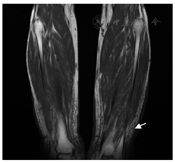

11例(41%)患者确诊黏液性水肿时无明显症状,2例(5%)患者曾被误诊为"结节性红斑" 。23例(85%)表现为双侧胫前黏液性水肿,其余4例(15%)患者双侧胫前、双手同时受累。6例(22%)患者同时有杵状指。14例患者确诊时具体描述了黏液性水肿的性质,其中5例患者有皮肤增厚,5例患者有色素沉着,7例患者有结节样改变,3例患者有斑块样皮肤病变。图1展示了黏液性水肿患者的临床特征,可见胫前局部皮肤增厚,有隆起的结节,类似于象皮腿样外观,局部有皮肤色素沉着及色素脱失(该患者同时合并白癜风)。双手可见杵状指样改变。影像学检查见黏液性水肿部位局部皮肤软组织水肿(图2)。其中3例患者行黏液性水肿处局部组织活检,病理可见表皮增生肥厚,真皮浅层胶原稀疏,较多黏液样物质沉积,阿辛蓝染色均为阳性(图3)。

注:箭头示双侧胫前软组织水肿